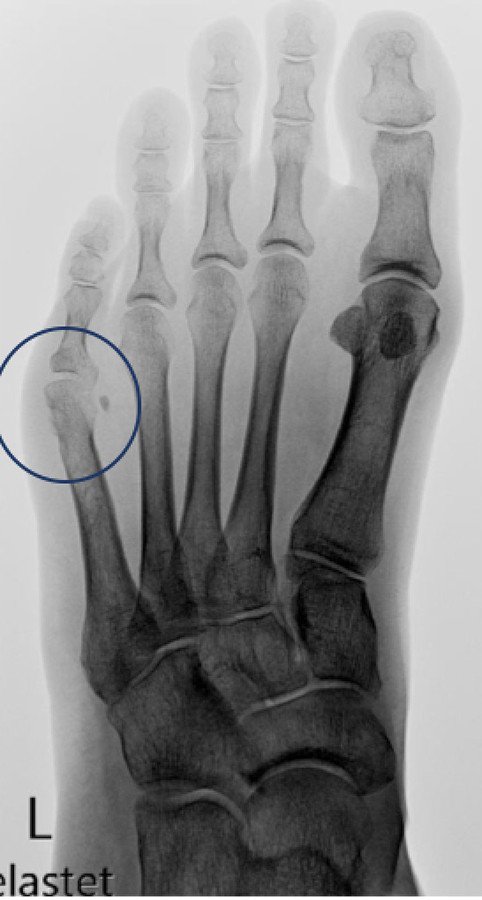

Bunionette-Deformität

Abb. 1: Bunionette-Deformität mit Abweichen des 5. Mittelfussknochens nach aussen vor der auswärts durchgeführten Abtragung des «Überbeins»

Bei der Bunionette-Deformität – auch Schneiderballen genannt – handelt es sich um eine Fehlstellung des 5. Mittelfussknochens mit aussenseitiger Verbreiterung des Fusses. Nicht alle Betroffenen entwickeln Beschwerden, unter Umständen können sich aber zunehmend unerträgliche Druckschmerzen in geschlossenen Schuhen entwickeln, die die Patienten zum Arzt führen. Klinisch zeigt sich eine Rötung seitlich am 5. Mittelfussköpfchen, nicht selten begleitet von einer schmerzhaften Schleimbeutelentzündung.

Die Ursache dieser spezifischen Beschwerden ist nicht die Entwicklung eines vermeintlichen Überbeins, sondern vielmehr eine zunehmende Fehlstellung des 5. Mittelfussknochens «nach aussen». Das «Überbein» entspricht einer ganz normalen anatomischen Struktur, nämlich dem 5. Mittelfussköpfchen. Demzufolge ist es ein Fehler, dieses «Überbein» abzutragen, auch wenn dies als einfachste Lösung nahegelegt wird. Vielmehr muss der 5. Mittelfussknochen, der eine wichtige tragende Funktion hat, nach «innen» gerichtet werden, um ihm seine normale anatomische Stellung wiederzugeben.